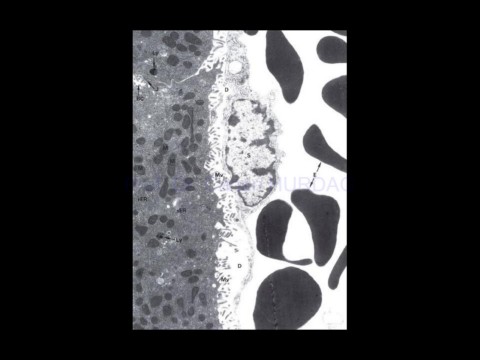

Page 80 - SİNDİRİME BAĞLI BEZLER

28-Apr-20                                          Sindirime ait bezler,                                                   80